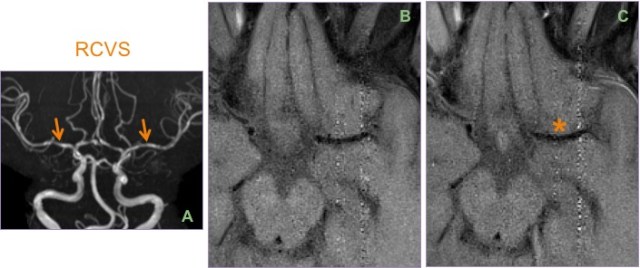

MIP-MRA (A) showing diffuse beading of the A1 & M1 segments & distal branches. Based on the clinical presentation and imaging findings, a diagnosis of reversible cerebral vasoconstriction syndrome (RCVS) was suggested.

Reversible vasospasm is essential for diagnosis; irreversibility suggest vasculitis. Follow-up DSA/MRA can be performed to demonstrate reversibility. On vessel wall imaging, RCVS will not enhance as opposed to vasculitis, and this can be performed to differentiate between the two if there is a doubt.

Contrast this case of RCVS (A), where there is no abnormal enhancement * of the wall of the vasoconstricted M1 segment between the pre (B) and post (C) VW images.